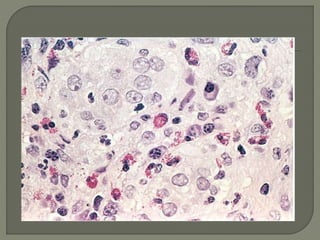

Purulent inflammation. A, Multiple bacterial abscesses in the lung, in

a case of bronchopneumonia. B, The abscess contains neutrophils

and cellular debris, and is surrounded by congested blood vessels

This type ofinflammation is characterized by the production of large amounts of pus or purulent exudate consisting of neutrophils, liquefactive necrosis, and edema fluid. Certain bacteria (e.g., staphylococci) produce this localized suppuration and are therefore referred to as pyogenic (pus-producing) bacteria

Purulent inflammation. A,Multiple bacterial abscesses in the lung, in a case of bronchopneumonia. B, The abscess contains neutrophils and cellular debris, and is surrounded by congested blood vessels